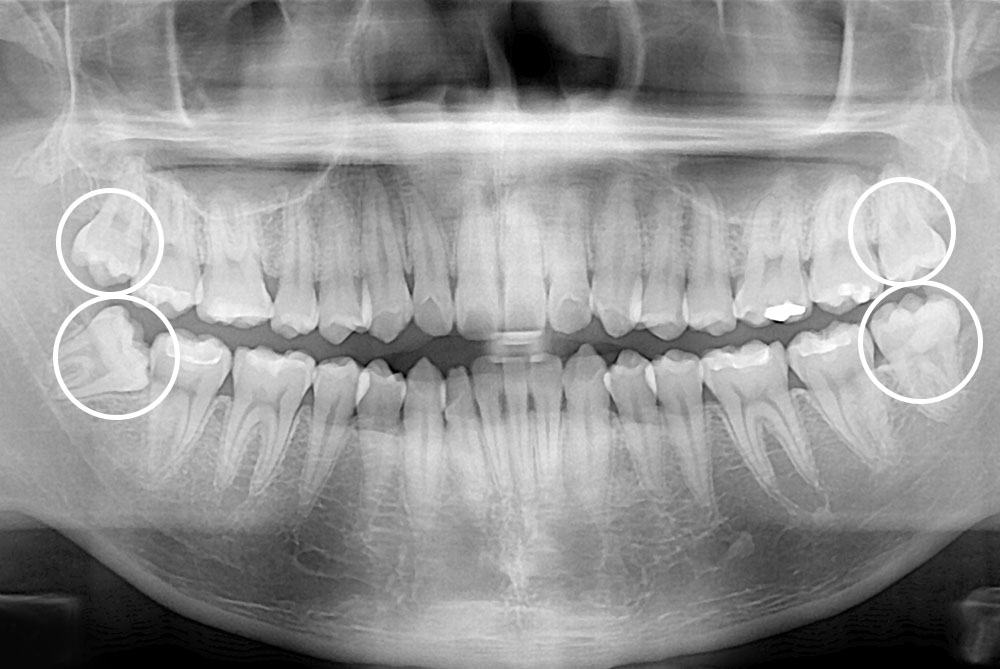

[사랑니] 매복 사랑니 발치

치료후 : 2023-03-16

세종치과는 구강악안면외과학 박사이신 원장님이 발치하는 치과입니다.